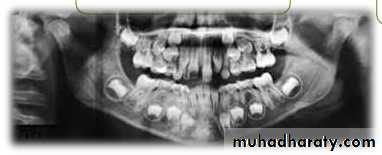

Periapical

Mandibular archOPG

Lateral ceph

Extraoral

RADIOGRAPHS

I. Qualitative radiographs

Maxillary archOcclusal

PAview

Max. ant. occlusal

Parallax method

OPG

Panoramic radiographs are basic radiograph

for assessment of impacted teeth•

•

Tooth position whether deep or shallow

General orientation horizontal or inclined

mesially/distallyRelationship with neighbouring teeth

Risk of their transpositionPresence or absence of apical resorption of

roots of adjacent teeth